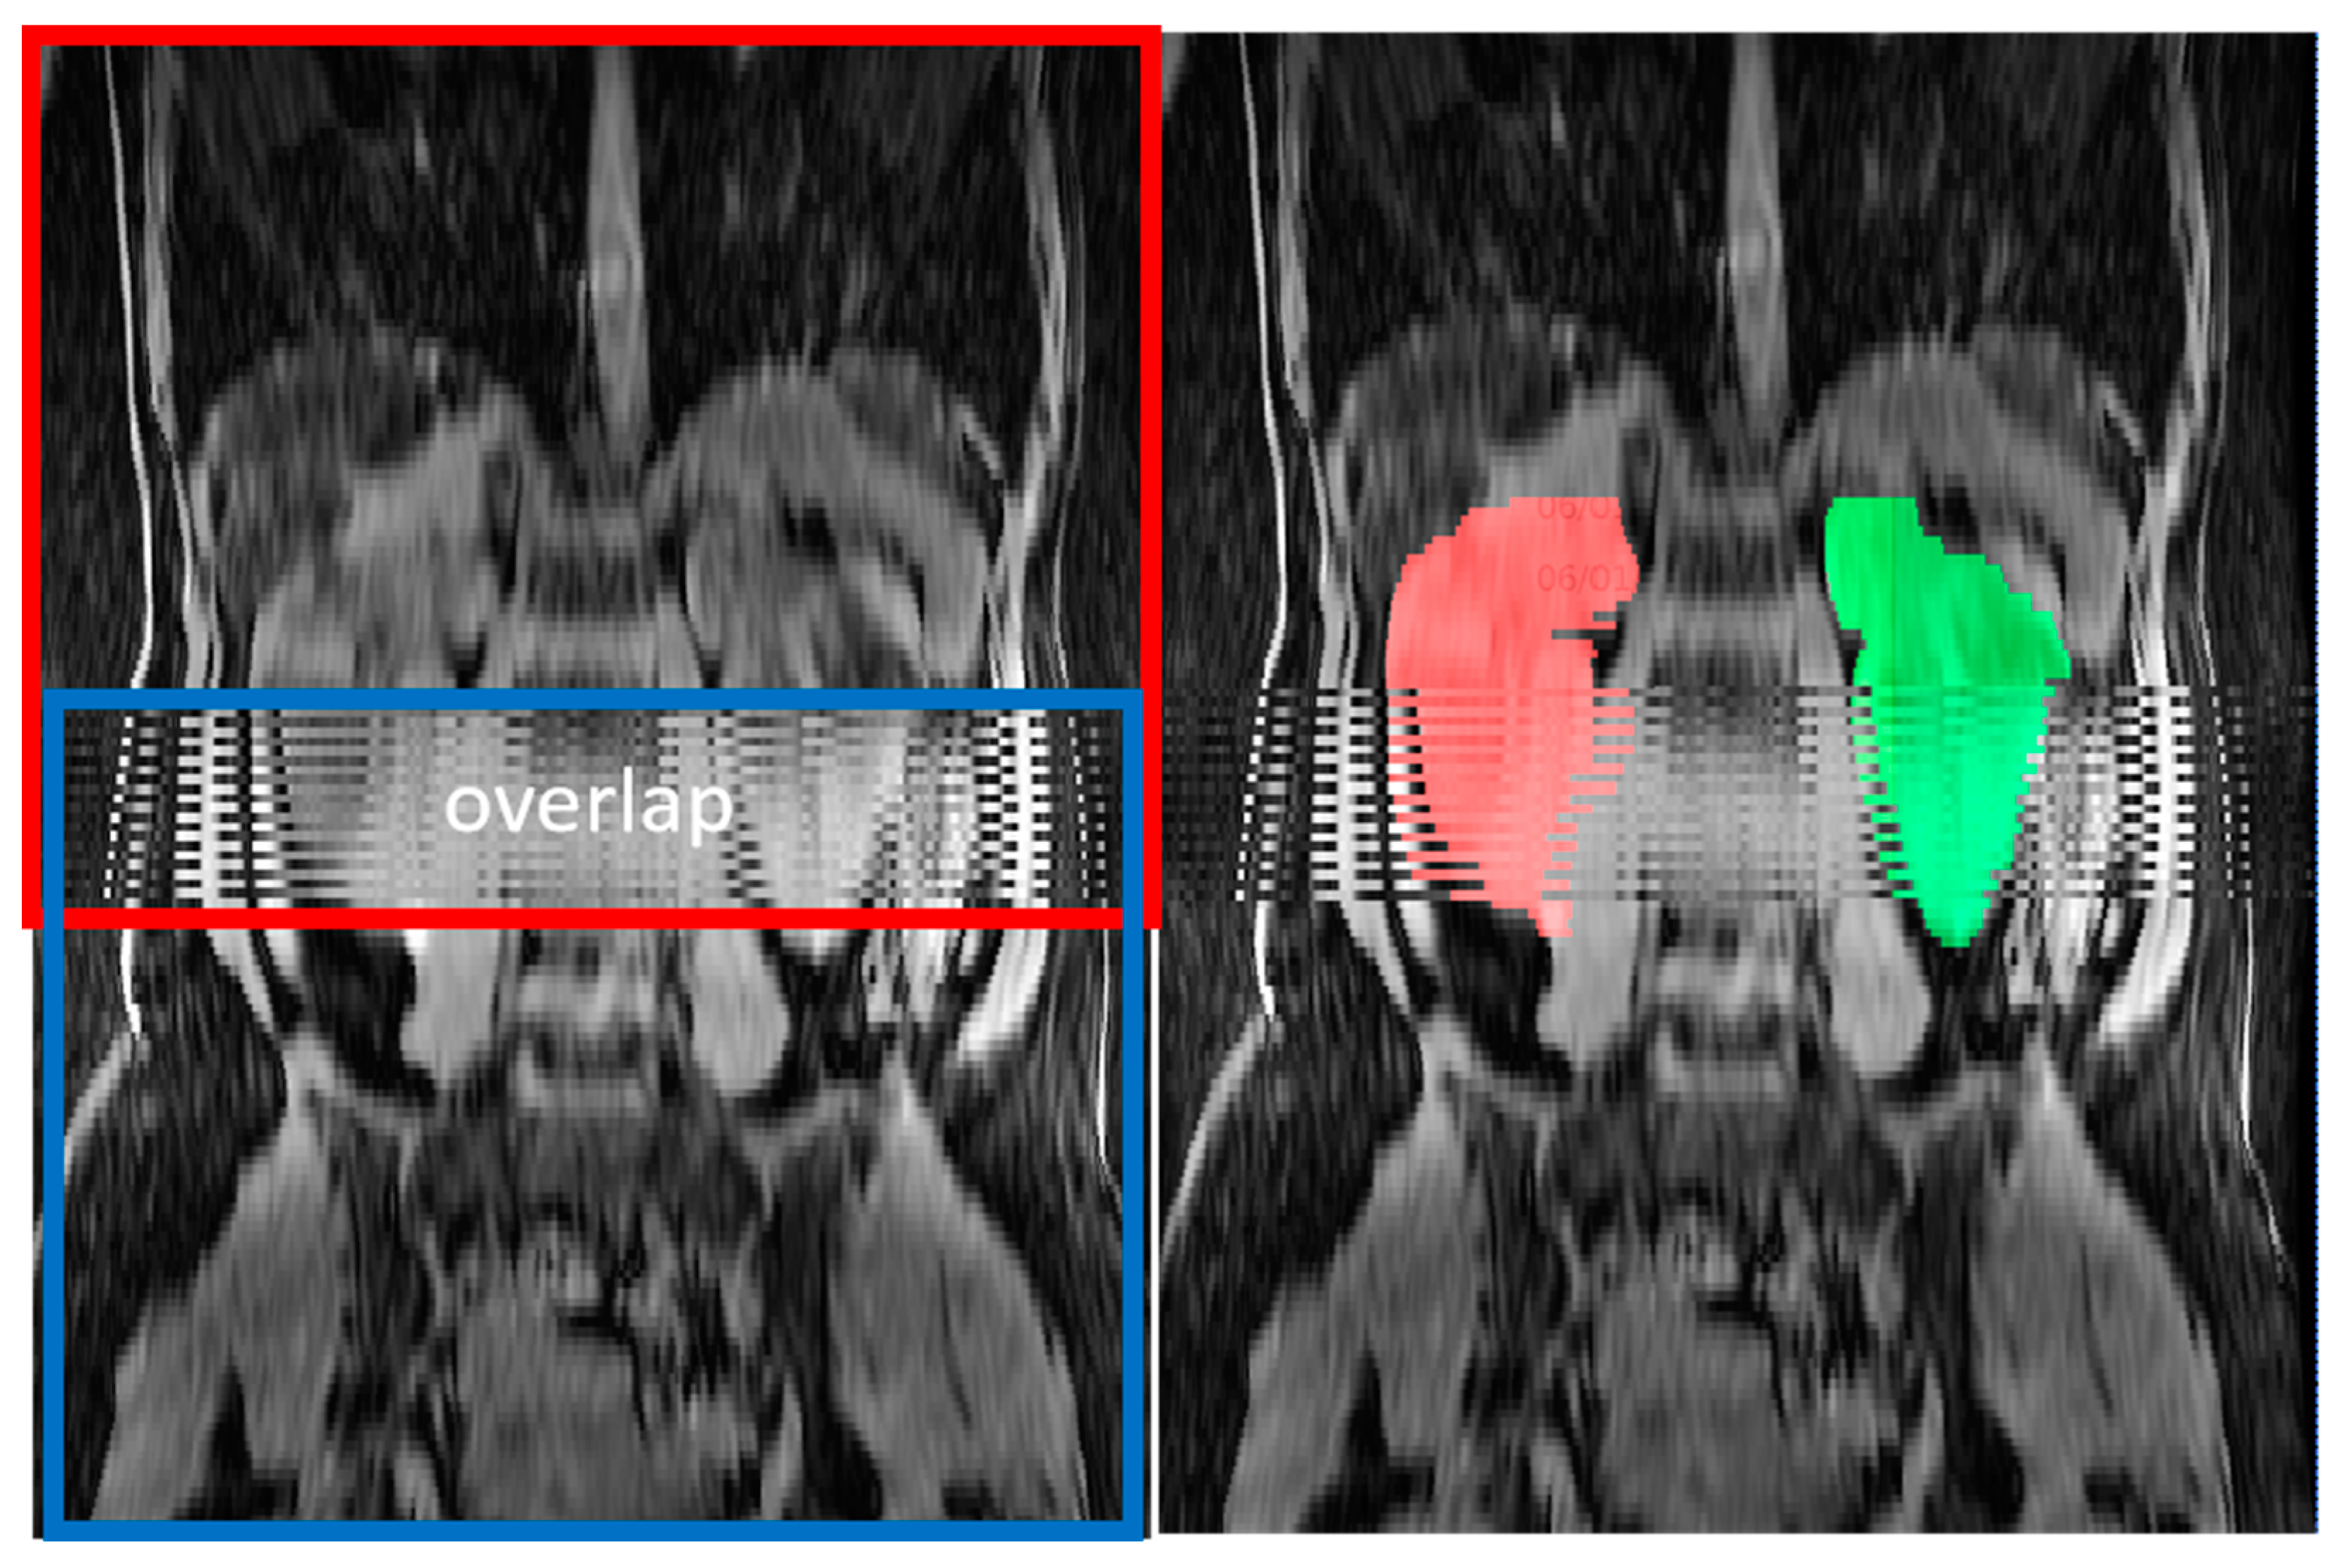

Composing errors from overlapping acquisitions exhibited alternating strips (Figure 5) on orthogonal reformations. We identified composing errors in 17 exclusively axial MRI pulse sequences, including six axial T2 sequences, seven axial T1 sequences, and four axial SSFP sequences, representing 3% of pulse sequences and 11% of exams. These composing errors led to an overestimation of TKV relative to the reference TKV, with a median of 8.7% and a range from 2.5% to 29%.

Figure 5. Composing errors from combining two, red and blue, overlapping acquisitions. In the region of overlap, the calculated organ volumes are erroneously doubled. This can be repaired by re-ordering the slice order and adjusting slice thickness based on the actually calculated spacing between slices. Right kidney is labeled in red. Left kidney is labeled in green.